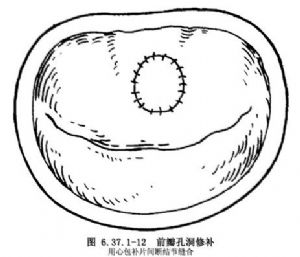

②瓣叶缺如:后瓣叶缺损或局限发育不良将该处瓣膜边缘矩形切齐,对缘缝合,相应部位的瓣环折叠。Carpenrtier 1988年设计的修复方法是将瓣缘切齐后,将后瓣沿两侧瓣环上切开,对缘缝合,相应瓣环折叠后,再将后瓣缝在瓣环上,称为滑行瓣叶手术方法(sliding leaflet techique)(图6.37.1-10)。前瓣孔洞是局限性瓣叶缺损,可直接心包补片修补(图6.37.1-11)。